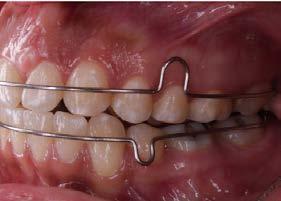

Durante la fase de trabajo se realizaron sets de intrusión y utilización de close coil; una vez cerrado el espacio entre los incisivos laterales, se indicó el uso de elásticos de clase III 3/16 4.5 oz para corregir la mordida borde a borde (Figura 4).

Se remitió a la especialidad en prostodoncia para valoración, indican abrir espacios en anteriores para su posterior restauración. Se retiró aparatología fija y se entregó retención con circunferenciales y fijo inferior (Figura 5).

Posteriormente se remitió a la especialidad de periodoncia y prostodoncia para su rehabilitación final con un reposicionamiento del frenillo superior y carillas de 3-3.

Como resultado se logró cumplir con los objetivos establecidos al inicio del tratamiento, se liberó el apiñamiento y se logró hacer el cierre de la mordida anterior (Figura 6A), así como la

mejora en la estética de la sonrisa lo cual impacto positivamente en la autoestima de la paciente. Se estableció una clase I molar y canina, se obtuvo un correcto overjet y overbite, las líneas medias coincidieron y se establecieron correctas guías anteriores (Figura 6B).